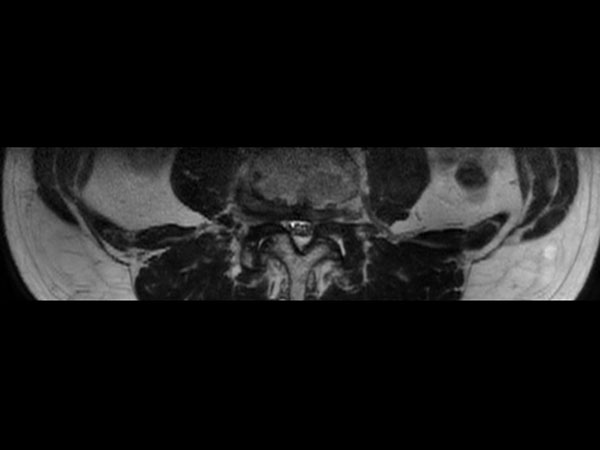

Lumbar Spine disc herniation

Patient with a lumbar spine disc herniation.